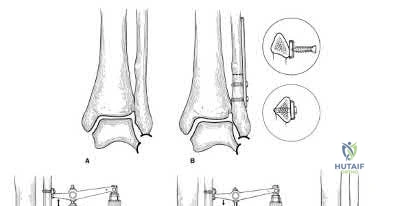

Correct Answer: 2-5 cm above the joint line

Explanation:

A syndesmotic screw should be placed parallel to the tibial plafond, typically 2 to 5 cm above the ankle joint line. It should be directed approximately 20 to 30 degrees anteriorly from the fibula to the tibia to account for the relative position of the bones.